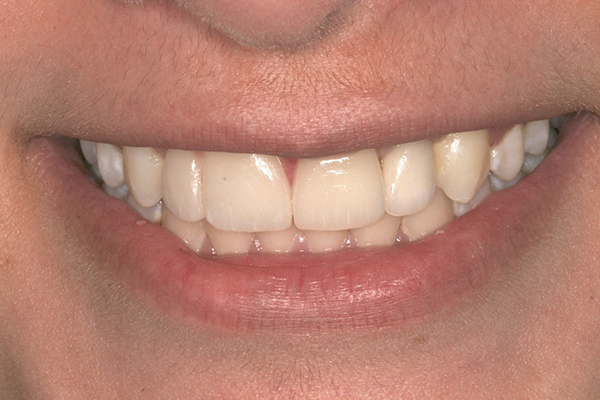

Fig 1 and Fig 2. Pretreatment photographs. Patient at 9 years of age on presentation.

A 9-year-old girl, referred to a prosthodontic office by her pediatric dentist, presented with her mother’s chief complaint: “The kids are teasing her about her big front tooth.” Findings from radiographic and clinical examinations revealed fused maxillary central-peg lateral incisors, teeth Nos. 7 and 8, and a congenitally missing lateral incisor, tooth No. 10 (Figure 1 through Figure 3). An implant was selected as the ideal treatment to replace tooth No. 10 when somatic growth was complete. A diagnostic wax-up was fabricated to determine if the fused tooth could be made to resemble two teeth, using pink composite to give the illusion of an interproximal papilla. The patient was referred for an orthodontic consultation to plan for closure of the diastema between teeth Nos. 8 and 9 and achievement of proper alignment for implant No. 10. The patient was also referred to a periodontist for pretreatment assessment of the tooth No. 10 site. An endodontist was consulted should exposure of the large pulp occur during tooth preparation.